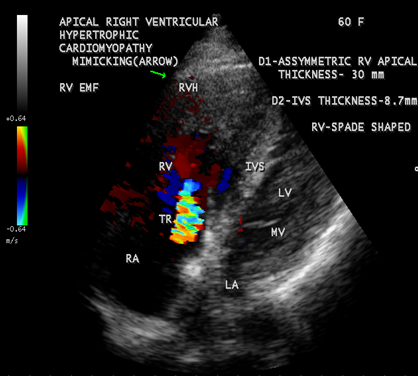

Case 7 Apical right ventricular hypertrophic cardiomyopathy in a 60- year old female mimicking as right ventricular EMF as shown in Figure 26.

Figure 26: Apical Right ventricular hypertrophic cardiomyopathy (asymmetric lateral wall hypertrophy with a thickness of 30 mm) mimicking as right ventricular endomyocardial fibrosis in a 60- year old female. (rugose border, a characteristic feature of EMF is absent and mild tricuspid regurgitation)

A left ventricular EMF mimicking apical left ventricular hypertrophic cardiomyopathy in a year-old boy as shown in Figures 23, 24 and 25 in a 2-year old male child and an apical right ventricular cardiomyopathy in a year-old female as shown in Figure 26 mimicking as right ventricular EMF have been found by Transthoracic echocardiographic screening. A right ventricular EMF associated with Psoriasis as shown in Figure 3 to7 in a 52- year old male and a left ventricular EMF associated with pemphigus in a 63- year old male as in Figure 39 were detected in this region of Thoothukudi.